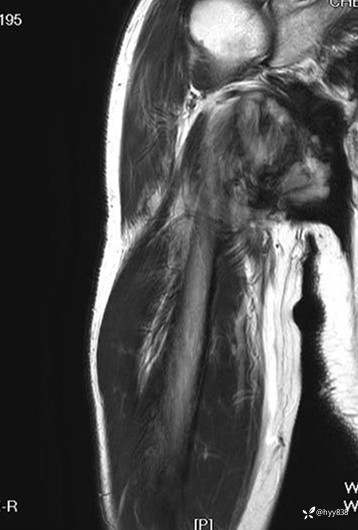

COR T2WI